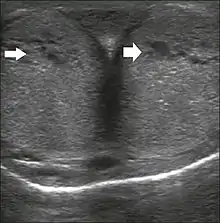

Penile ultrasonography with doppler can be used to examine the erect penis. Most cases of ED of organic causes are related to changes in blood flow in the corpora cavernosa, represented by occlusive artery disease (in which less blood is allowed to enter the penis), most often of atherosclerotic origin, or due to failure of the veno-occlusive mechanism (in which too much blood circulates back out of the penis). Before the Doppler sonogram, the penis should be examined in B mode, in order to identify possible tumors, fibrotic plaques, calcifications, or hematomas, and to evaluate the appearance of the cavernous arteries, which can be tortuous or atheromatous.[45]

Erection can be induced by injecting 10–20 µg of prostaglandin E1, with evaluations of the arterial flow every five minutes for 25–30 min (see image). The use of prostaglandin E1 is contraindicated in patients with predisposition to priapism (e.g., those with sickle cell anemia), anatomical deformity of the penis, or penile implants. Phentolamine (2 mg) is often added. Visual and tactile stimulation produces better results. Some authors recommend the use of sildenafil by mouth to replace the injectable drugs in cases of contraindications, although the efficacy of such medication is controversial.[45]

Before the injection of the chosen drug, the flow pattern is monophasic, with low systolic velocities and an absence of diastolic flow. After injection, systolic and diastolic peak velocities should increase, decreasing progressively with vein occlusion and becoming negative when the penis becomes rigid (see image below). The reference values vary across studies, ranging from > 25 cm/s to > 35 cm/s. Values above 35 cm/s indicate the absence of arterial disease, values below 25 cm/s indicate arterial insufficiency, and values of 25–35 cm/s are indeterminate because they are less specific (see image below). The data obtained should be correlated with the degree of erection observed. If the peak systolic velocities are normal, the final diastolic velocities should be evaluated, those above 5 cm/s being associated with venogenic ED.[45]